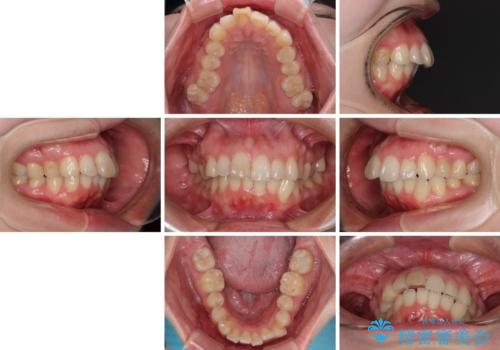

カリエール・ディスタライザーを併用したインビザライン矯正治療

- 30代女性

- インビザライン

- 治療期間

- 2年6ヶ月

- 上顎前歯の突出感と、前歯のクロスバイトを気にして来院された患者様です。

前歯の叢生と口元の閉じにくさを気にして来院された患者様です。

奥歯の咬み合わせを見ると、上顎が下顎に対して相対的に前方にありました。

口元の閉じにくさを改善するためには、上顎臼歯を後方に移動させた咬み合わせにする必要があります。

インビザライン単体で改善することも可能ですが、達成する可能性が高くないため、カリエールディスタライザーという補助装置を併用して、より確実性を上げることとしました。

奥歯の咬み合わせを改善しながら、並行してインビザラインで歯列を整えることとしました。

カリエール・ディスタライザーを用いたことで上顎前歯の突出感はスムーズに解消され、歯列不正は1年半ほどでほぼ改善することができました。

しかし、その後インビザライン特有の奥歯がうまく噛めないという問題が長引き、改善に1年近い期間を要することとなりました。